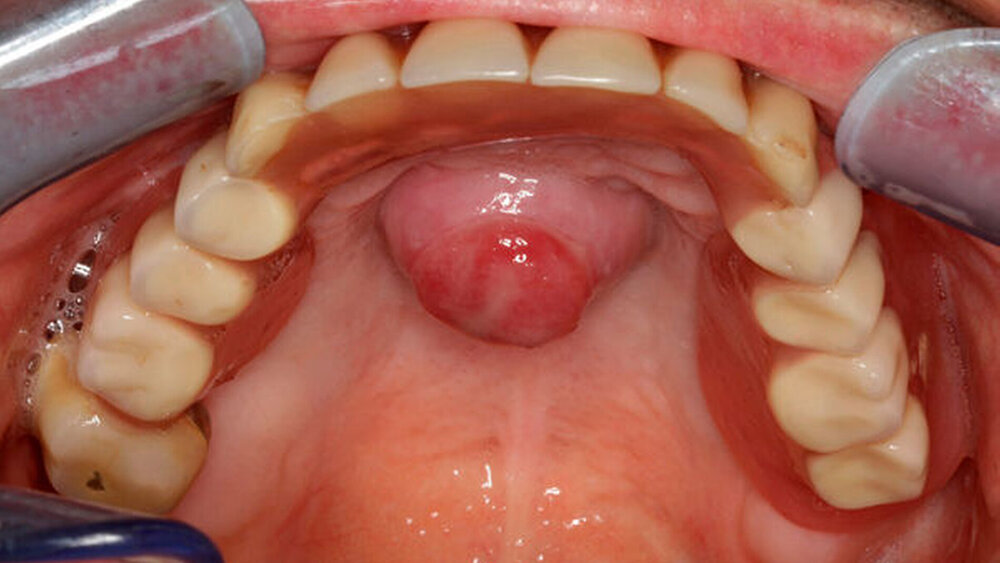

Bei unauffälligem extraoralen Befund imponierte intraoral ein 2 cm x 2 cm großer, zentral im Bereich des harten Gaumens gelegener Tumor (Abbildung 1). Die Raumforderung zeigte sich palpatorisch weich, nicht verschieblich, nicht fluktuierend und prall-elastisch. Die Mundschleimhaut wies in regio 044 und 048 bei Zustand nach operativer Therapie einer Osteonekrose eine narbige Veränderung auf.